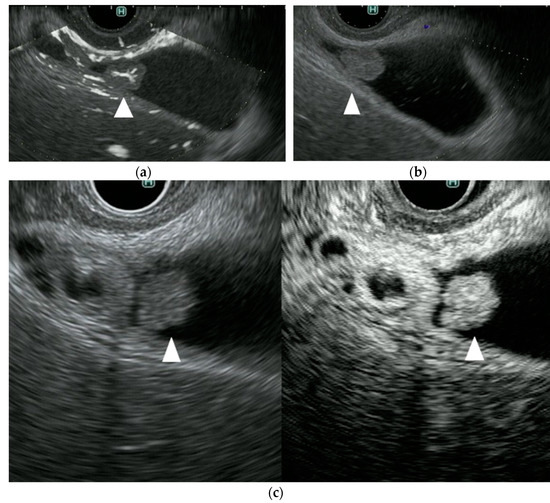

Figure 3 from New Imaging Techniques for Endoscopic Ultrasonography Endoscopic Ultrasound Imaging Techniques Endoscopic ultrasound (eus) has become an important diagnostic modality for the identification and risk stratification of. Endoscopic ultrasound is a procedure that combines endoscopy and ultrasound to create images of the digestive tract and nearby organs. Endoscopic ultrasound (eus), developed in the 1980s, was initially predominantly used for guidance of fine needle. Endoscopic ultrasound (eus) is now well established as. Endoscopic Ultrasound Imaging Techniques.